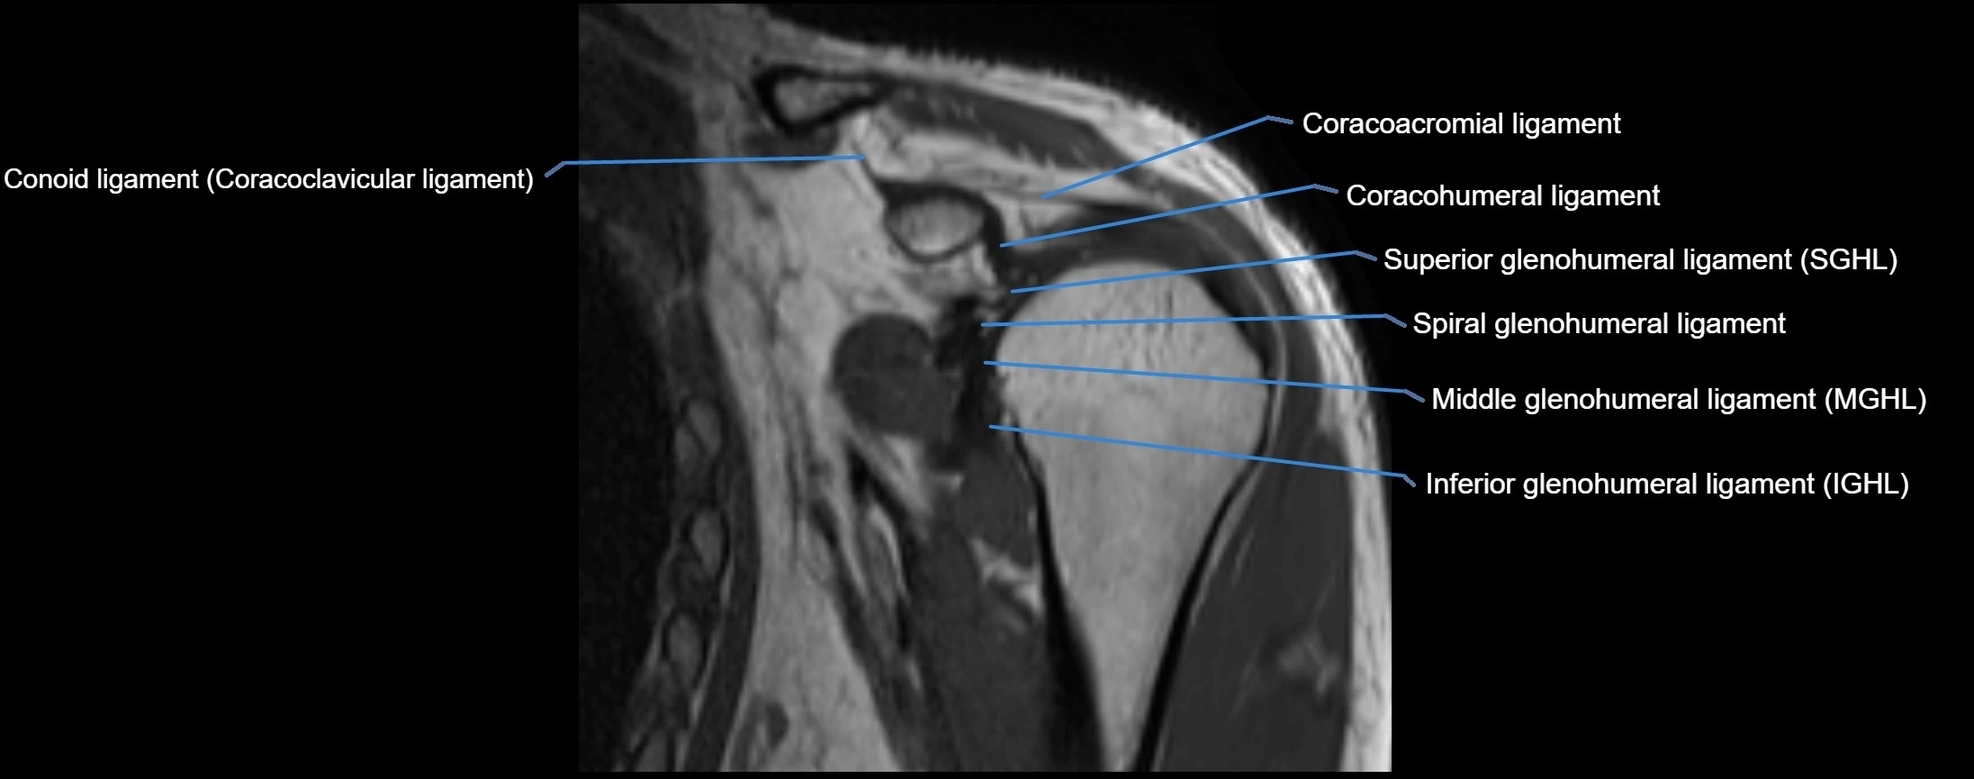

CT image

image